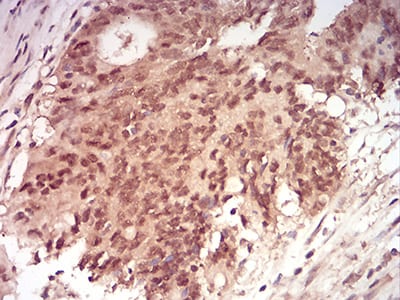

| IHC | 1/200 - 1/1000 | Human,Rat,Monkey |